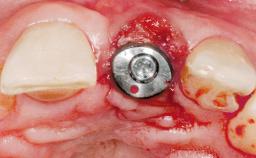

Type of Implants One-Piece

Attachment One-Piece

Placement Protocol Immediate implant placement

Socket Morphology Single-root socket